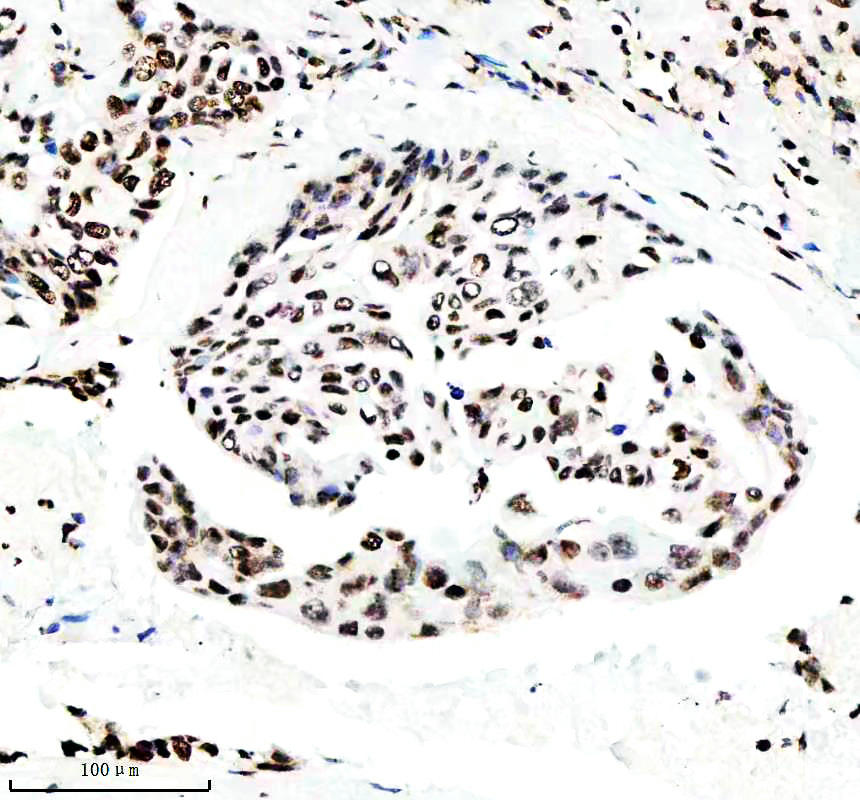

IHC analysis of Histone H3 (acetyl K14) using anti-Histone H3 (acetyl K14) antibody (BM4151) .

Histone H3 (acetyl K14) was detected in a paraffin-embedded section of human placenta tissue. The tissue section was incubated with rabbit anti-Histone H3 (acetyl K14) Antibody (BM4151) at a dilution of 1:200 and developed using HRP Conjugated Rabbit IgG Super Vision Assay Kit (Catalog # SV0002) with DAB (Catalog # AR1027) as the chromogen.

IHC analysis of Histone H3 (acetyl K14) using anti-Histone H3 (acetyl K14) antibody (BM4151) .

Histone H3 (acetyl K14) was detected in a paraffin-embedded section of human placenta tissue. The tissue section was incubated with rabbit anti-Histone H3 (acetyl K14) Antibody (BM4151) at a dilution of 1:200 and developed using HRP Conjugated Rabbit IgG Super Vision Assay Kit (Catalog # SV0002) with DAB (Catalog # AR1027) as the chromogen.